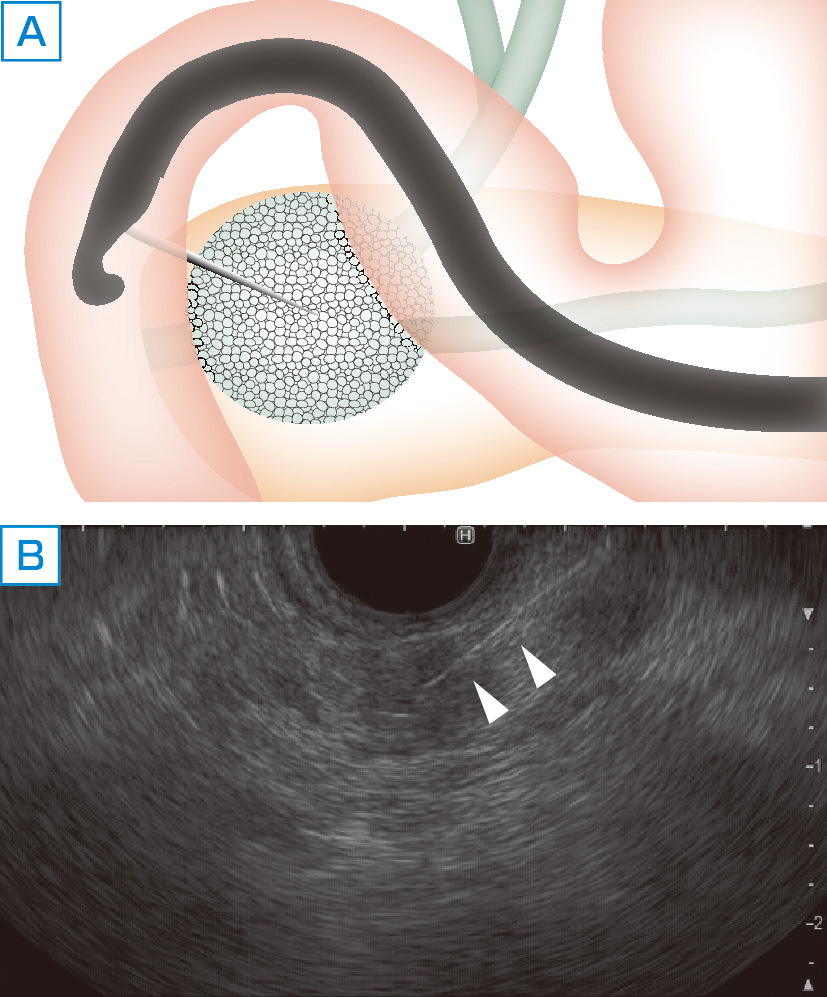

カラーアトラス新泌尿器科手術手技図譜 |本 | 通販 | Amazon

カラーアトラス新泌尿器科手術手技図譜 |本 | 通販 | Amazon

カラーアトラス新泌尿器科手術手技図譜 |本 | 通販 | Amazon,